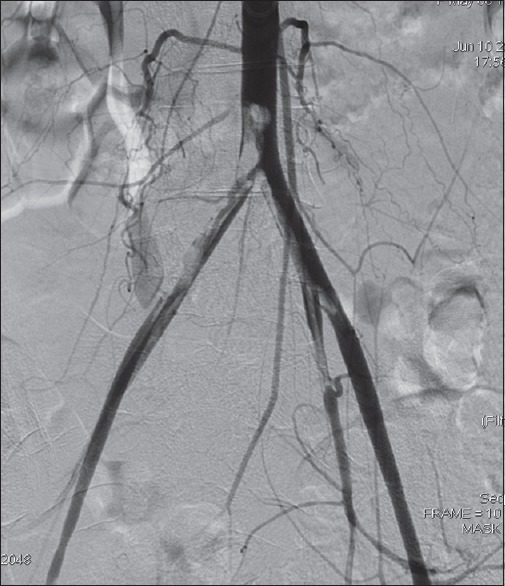

Materials and methods: We present our first 25 cases of peripheral angioplasty in Northwestern Nigeria. The clinical diagnosis of peripheral artery disease was confirmed with Doppler ultrasound and angiography. Angioplasty was done either through femoral or brachial artery approaches. The patients were monitored for minimum of 6 months with serial clinical and Doppler ultrasound examinations.

Results: Our patients consist of 19 males and 6 females. Their ages ranged from 20 to 80 years with a mean of 54 ± 17.5 years. There were 13 hypertensive and 15 diabetic patients while 5 patients have co-morbidities of diabetes and Hypertension. Although femoral antegrade route is the common access for angioplasty (14 out of 25), seven patients who were treated through the left brachial artery, six of them had either Type C or D aortoiliac disease in addition to distal lesions. At follow-up, 36% had limb amputation while one patient died a day after the procedure. Out of nine patients who had amputation, six are diabetic.